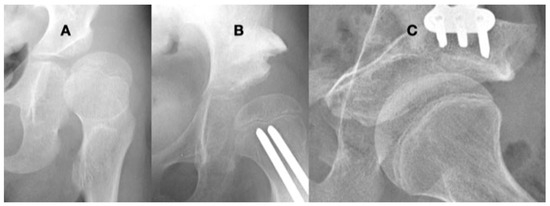

3.3.1. Impact of Abnormal Motor Function on Hip Development in Ambulatory Children

3.3.2. Pathology of Hip Development in Nonambulatory Children

3.3.3. Pathology of Hip Development in Children with Low Tone and Muscle Weakness